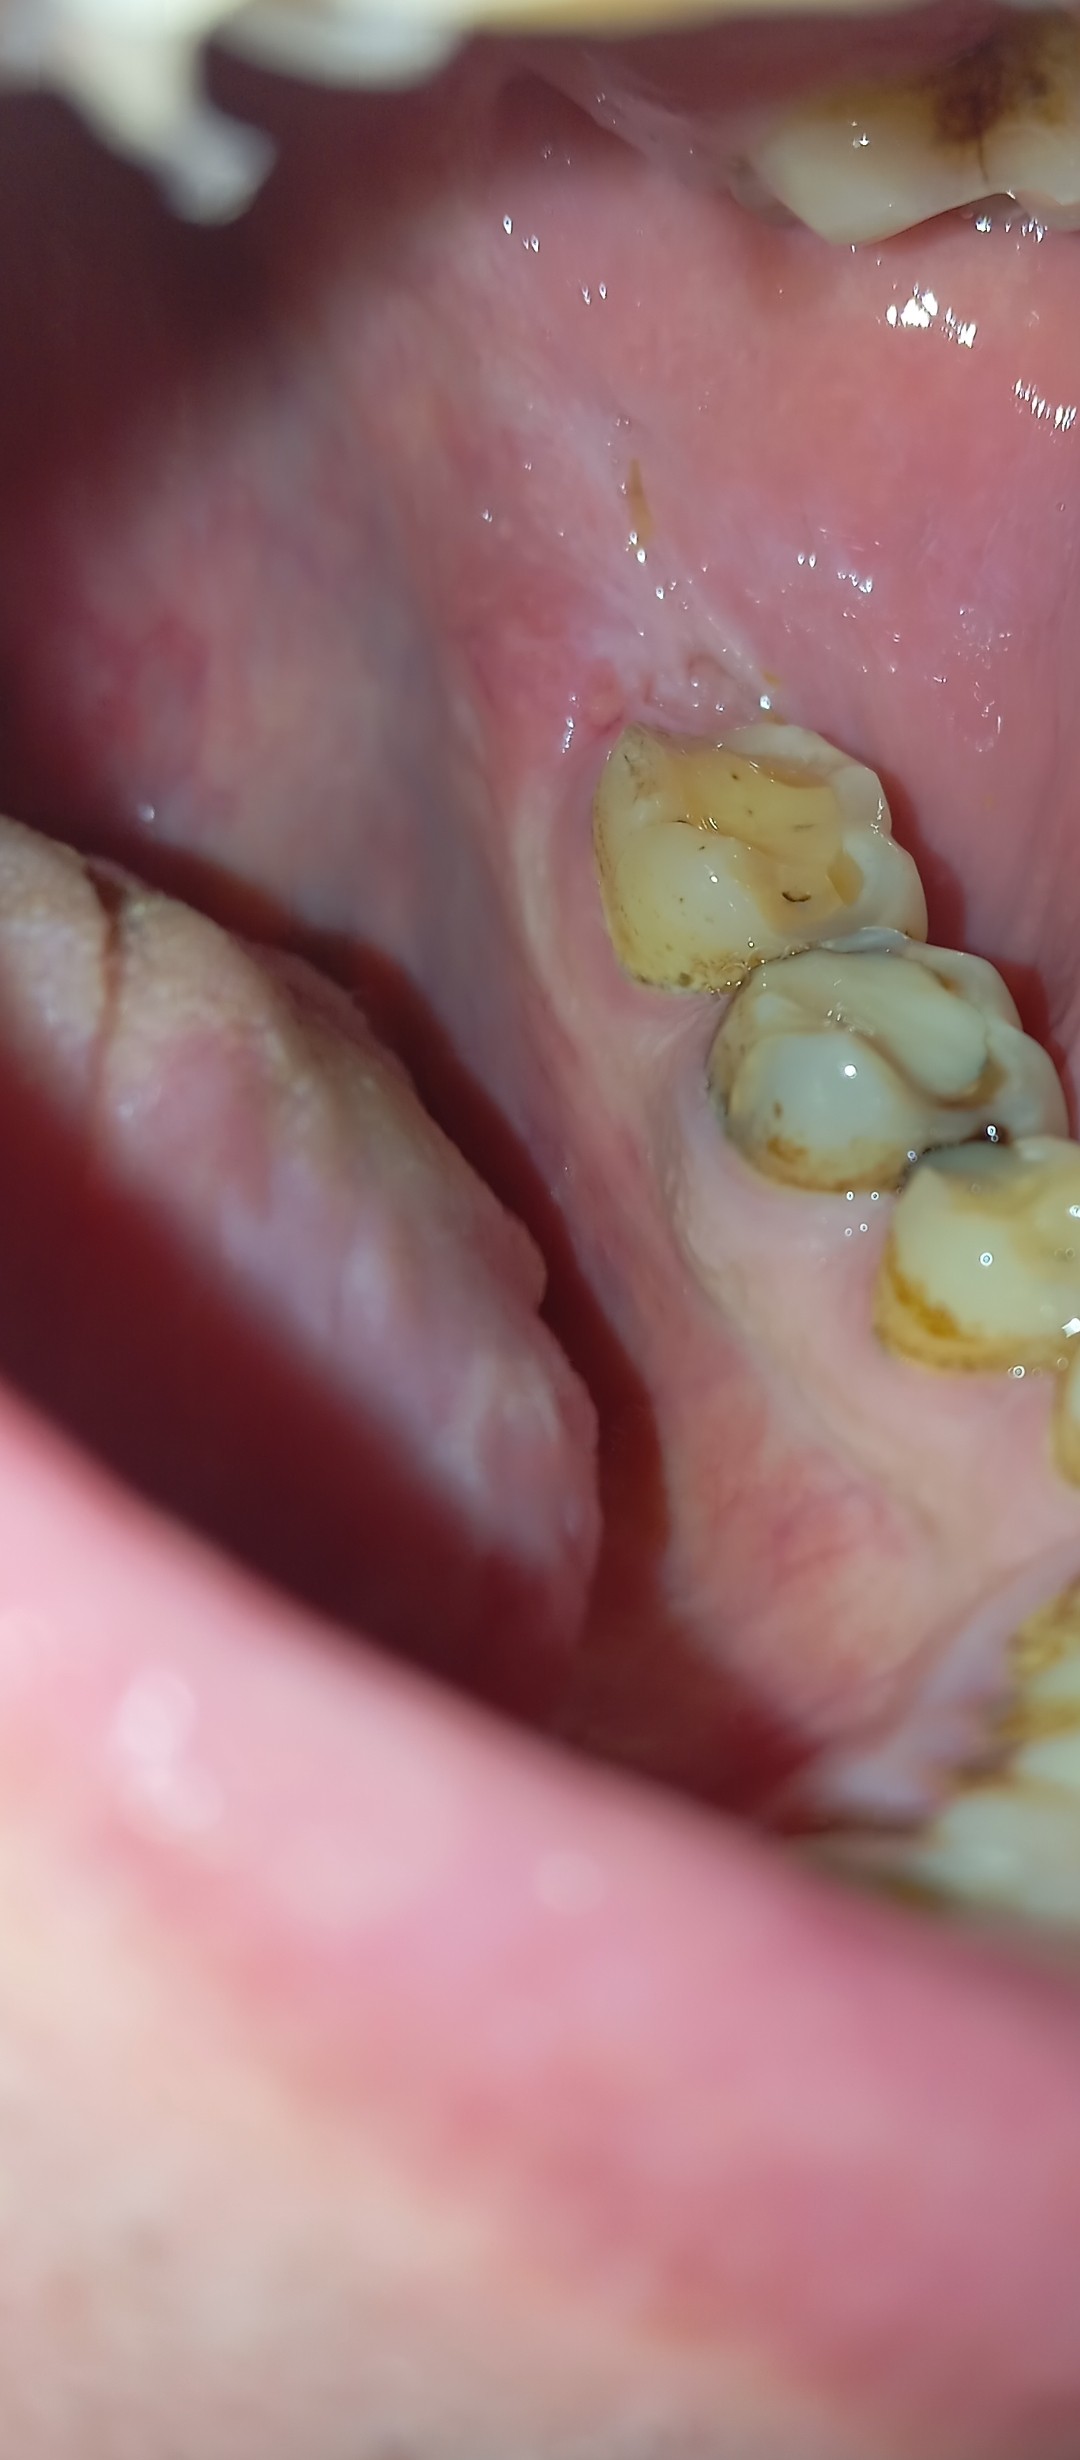

Добрый день. Неделю назад у меня начала болеть десна в нижнем ряду за седьмым зубом. Там как бы ранка Толи трещина и подпухло немного. Та восьмерка следит крепко. Мне 46 доктор говорил шо она уже не выйдет. Так вот через пару дней добавилась боль в шестом или седьмом зубе. Пульсирующая боль. Ночью не спал почти. Утром сегодня поехал к хирургу он удалил шестой зуб так как он плохой на снимке. Теперь я думаю решил ли я проблему, или это будет продолжаться и в е это из-за восьмёрки? Как думаете на снимке есть восполнение которое давало боль? Спасибо